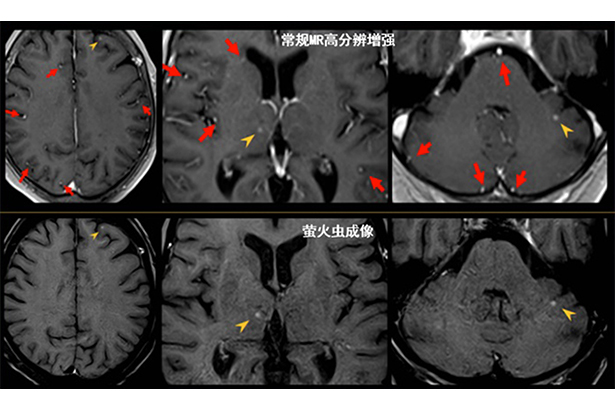

高分辨“螢火蟲”成像技術,可實現高空間分辨和超薄層(最小層厚0.2mm)全腦掃描,2-3 分鐘即可實現全腦3D 掃描,同時避免血管高亮信號的干擾,提升微小腫瘤的檢出率。